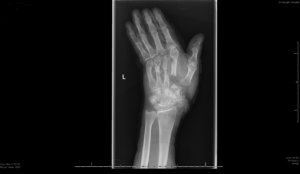

X-ray images before surgery (top) and after surgery (bottom)

Plastic surgeons at St George’s Hospital in Tooting have saved a man’s hand following seventeen hours of surgery, after a chop saw accident resulted in a double-level amputation.

Anthony, 46, from Walton-on-Thames, feared he would lose his hand after catching it in a chop saw while cutting flooring on Thursday 30 May.

Mr Adlard said: “When we took him to theatre I realised it was much worse than I’d first thought. It had been described as a sub-total hand amputation, which was true, however it had it been cut off almost completely in two places – at the base of his palm and again just below the fingers – resulting in a double-level amputation.”